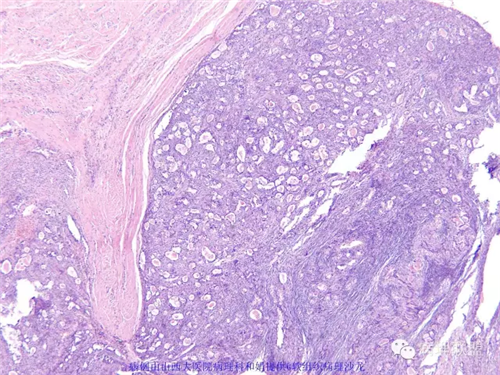

M,57岁,右膝关节外侧皮下肿物10余年,活动度好。

免疫组化结果阴性:S-100,SMA,Calponin,CD10,CD99,CD34,CEA,PHH3。

本例形态学上是非常典型的双相型滑膜肉瘤,滑膜肉瘤临床上大部分表现为生长缓慢的肿瘤。以青壮年多见,主要发生于四肢大关节附近,也可见于其他少见部位,如肺、肾等实质器官,形态学分为5种类型:单相纤维型、单相上皮型、双相型、低分化梭形细胞型和小细胞型。有文献报道个别患者有长达20年的病史。